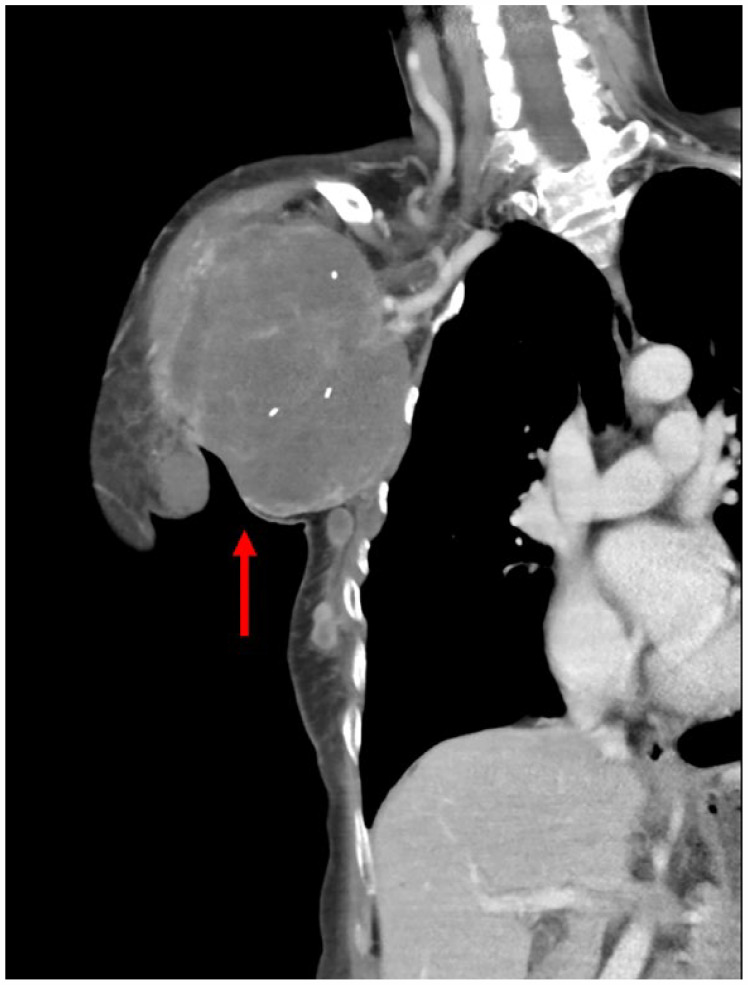

化生性乳腺癌是一种浸润性癌,肿瘤上皮向间质样上皮分化率高。它只占所有乳腺癌的不到1%。虽然80%至90%的化生性乳腺癌是三阴性癌症,但它们的预后通常比其他三阴性乳腺癌(tnbc)更差。化生癌对细胞毒性化疗也常常是难治的。在此,我们报告了一例61岁的女性患者,在右腋窝尾乳腺组织中表现为一个孤立的带梗肿块,活检显示化生性乳腺癌伴软骨样分化。新辅助化疗和免疫治疗均失败。尽管她接受了减体积手术,但手术前肿瘤的再生速度更快。尽管接受了姑息性化疗,患者还是在手术后11周死亡。这个病例引起医生的注意,早期识别和手术可能比化疗更有利于对抗化生乳腺癌。

Metaplastic breast carcinoma is an invasive carcinoma with a high differentiation rate of the neoplastic epithelium toward mesenchymal-like epithelium. It comprises of only less than 1% of all breast cancers. Although 80% to 90% of metaplastic breast carcinomas are triple-negative cancers, they usually have worse outcomes than other triple-negative breast cancers (TNBCs). Metaplastic carcinoma is also often refractory to cytotoxic chemotherapy. Here, we reported a case of a 61-year-old female patient, presenting with a solitary and pedunculated mass in the right axillary tail breast tissue, whose biopsy revealed metaplastic breast carcinoma with chondroid differentiation. She had failed neoadjuvant chemotherapy and immunotherapy. Although she received debulking surgery, the tumor regrew even faster before surgery. Despite receiving palliative chemotherapy, the patient died 11 weeks after surgery. This case draws attention to physicians that early recognition and surgery may be more beneficial than chemotherapy in combating metaplastic breast carcinoma.